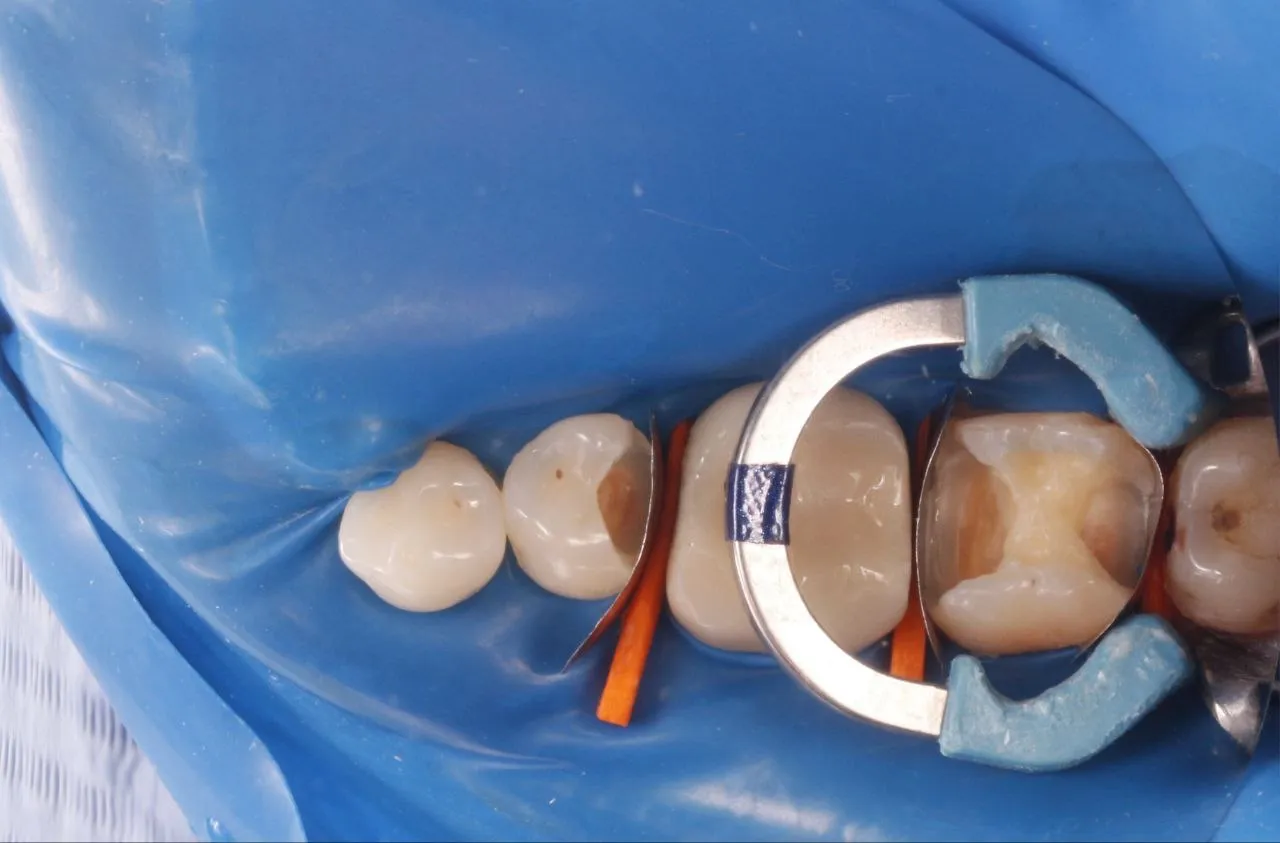

Лікування глибокого вторинного карієса зубів 17 та 16